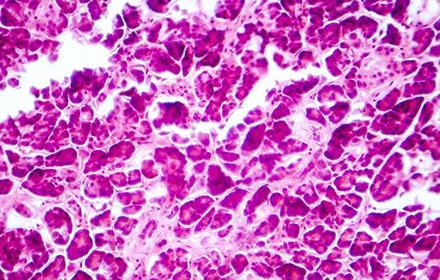

Pancreatic cancer link to worsening type 2 diabetes

14 mars 2017